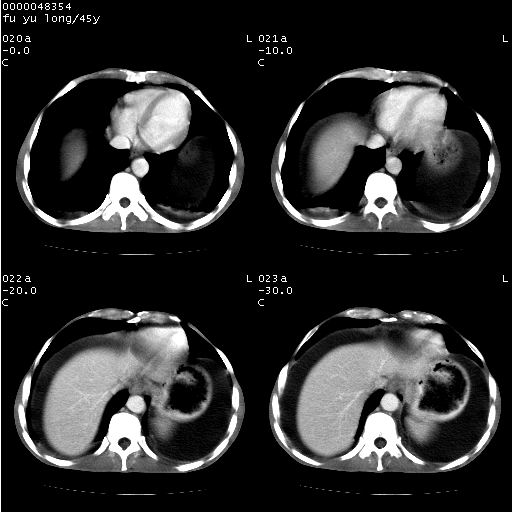

以下是引用医影拾贝在2008-5-30 2:38:00的发言:[br]气肿性胃炎、胃十二指肠溃疡、腹膜炎,考虑穿孔可能性较大

以下是引用lkc8963在2008-5-30 8:44:00的发言:[br]胃窦癌伴网膜(胃结肠韧带)/腹膜及腹膜后淋巴结转移.